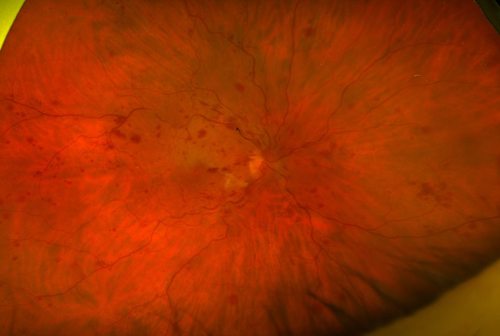

His right BCVA was now counting fingers (CF) and the left 6/6. His IOPs were 46mmHg in his right eye and 22mmHg in his left. In the right eye, new vessels on the iris (NVI) (Fig 1) and in the drainage angle (NVA) were identified. Posterior segment examination demonstrated retinal haemorrhages and venous tortuosity consistent with a central retinal vein occlusion (CRVO) (Fig 2). Additional findings on macula ocular coherence tomography (OCT) demonstrated an epiretinal membrane and cystoid macula oedema (CMO).

Fig 2. Fundus image demonstrating signs consistent with Right CRVO